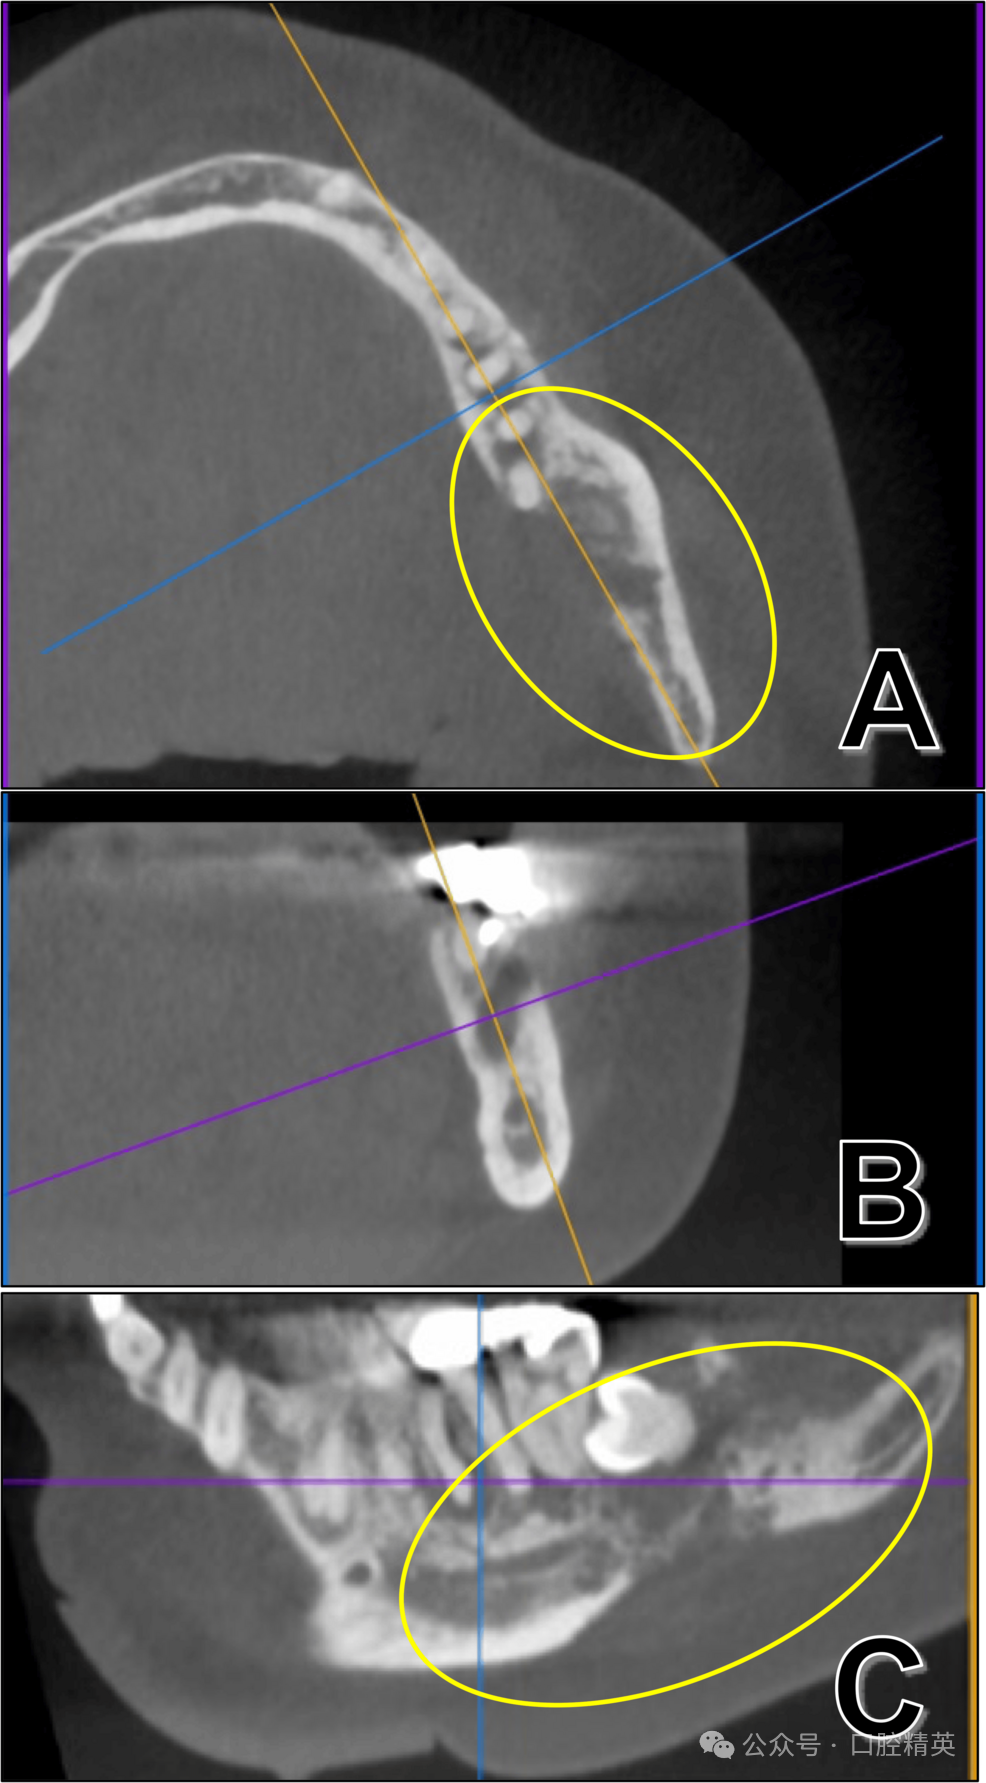

此外,病灶与左侧下颌下淋巴结关系密切,提示存在淋巴结直接侵犯可能(图6)。

图6:38牙拔除术后计算机断层扫描(软组织模式)

(A)及轴位(B)影像显示,病变(红色椭圆)与左侧下颌下淋巴结(黄色椭圆)关系密切,提示存在淋巴结直接侵犯可能。

增强磁共振成像(MRI)显示,38牙拔牙窝至下颌支区域可见早期强化肿块,侵犯翼下颌间隙,符合恶性肿瘤表现(图7)。

图7:增强磁共振成像

增强磁共振成像显示,38牙拔牙窝至下颌支区域可见早期强化肿块,侵犯翼下颌间隙,符合恶性肿瘤表现(黄色椭圆:高度提示恶性)。